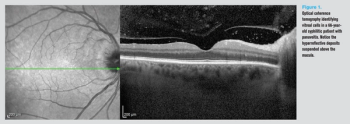

.png)